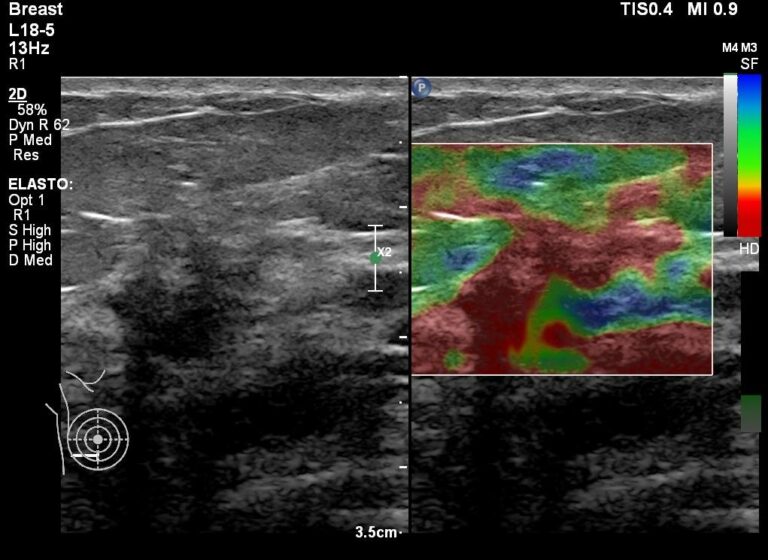

ΥΠΕΡΗΧΟΣ ΥΨΗΛΗΣ ΕΥΚΡΙΝΕΙΑΣ ΜΕ ΕΛΑΣΤΟΓΡΑΦΙΑ ΚΟΜΟΤΗΝΗ

ELASTOGRAFİ COMOTİNİ İLE YÜKSEK ÇÖZÜNÜRLÜKLÜ ULTRASON

HIGH DEFINITION ULTRASOUND WITH ELASTOGRAPHY COMOTINI